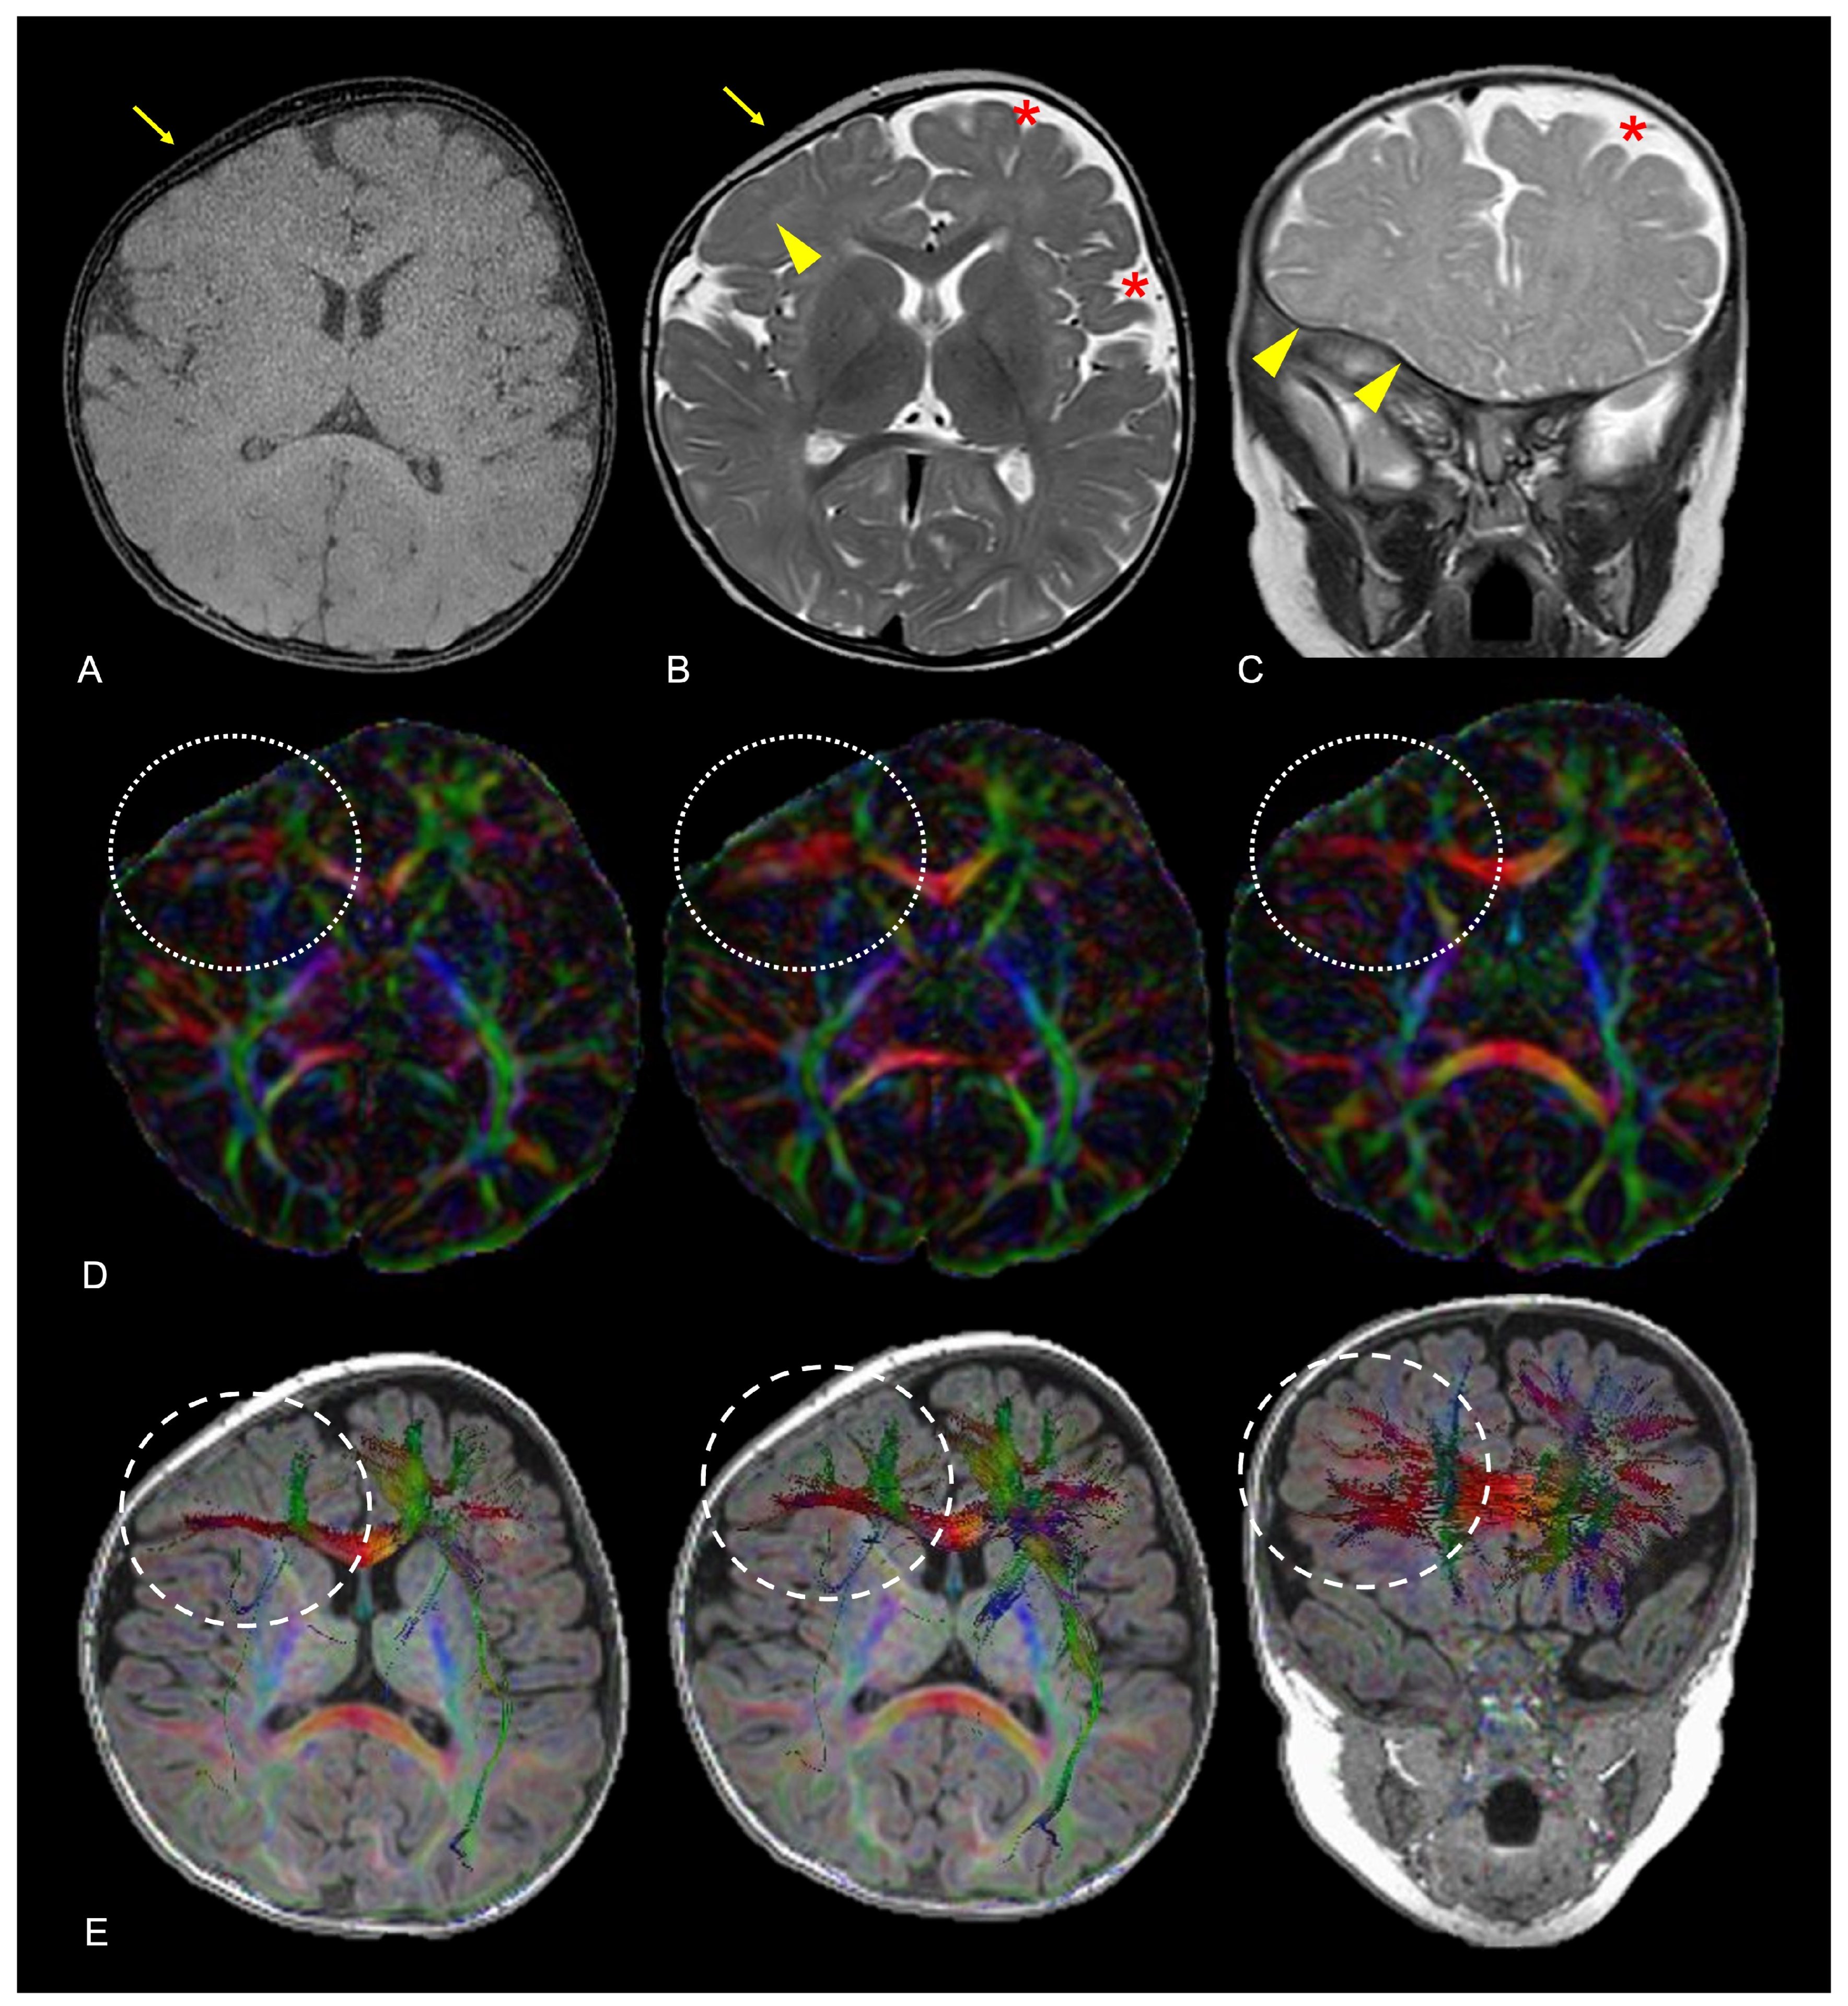

4.3. Microstructural Abnormalities and Possible Impacts on Brain Development